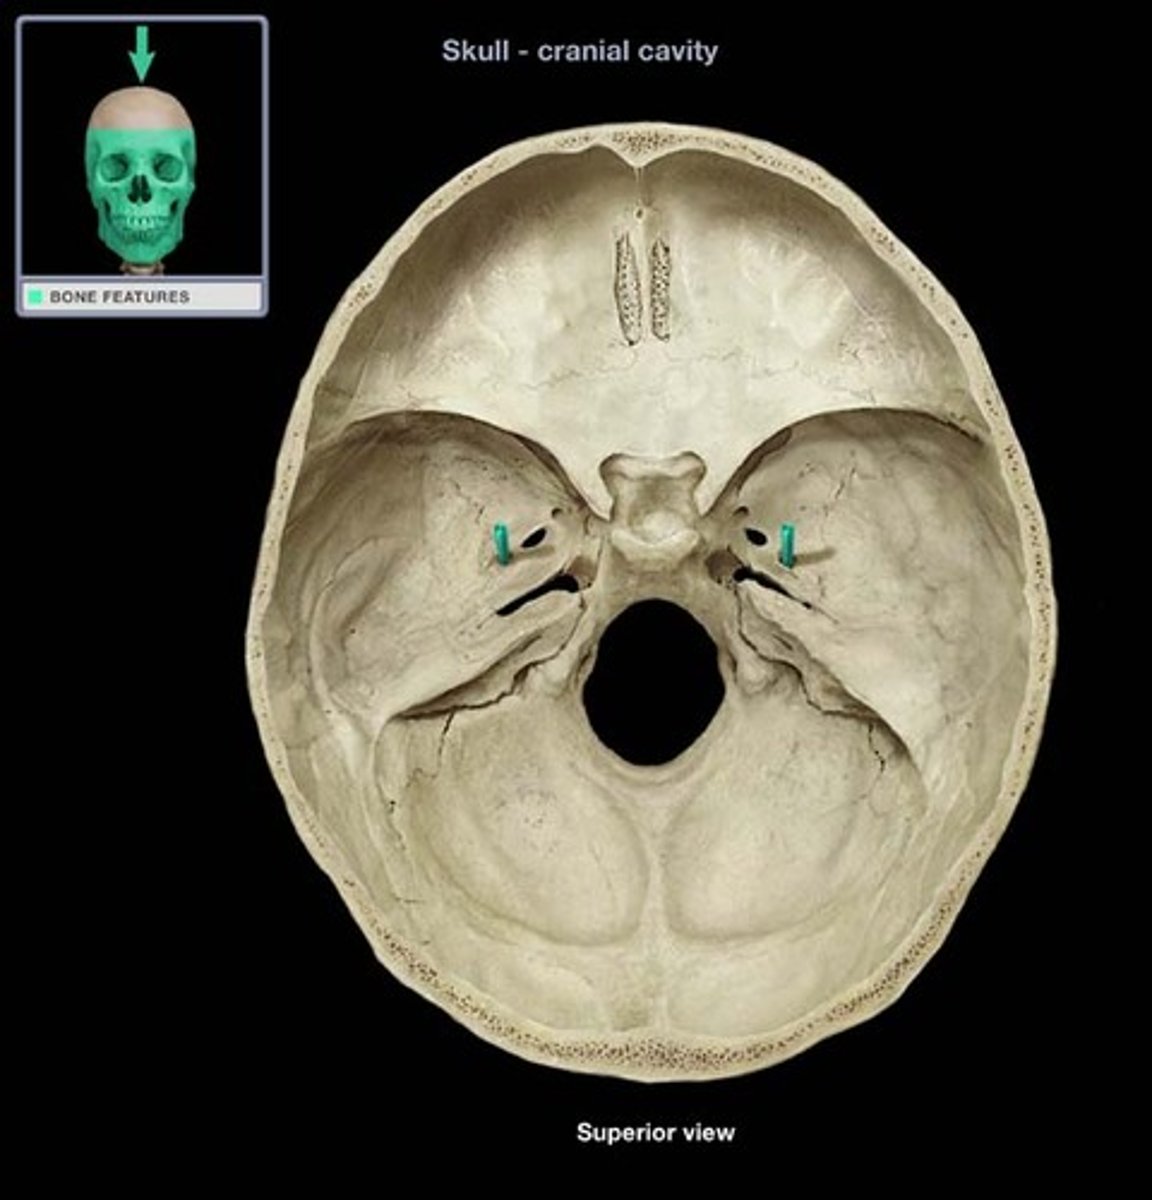

stylomastoid foramen

Name this structure.

carotid canal

jugular foramen

Name this structure.

internal acoustic meatus